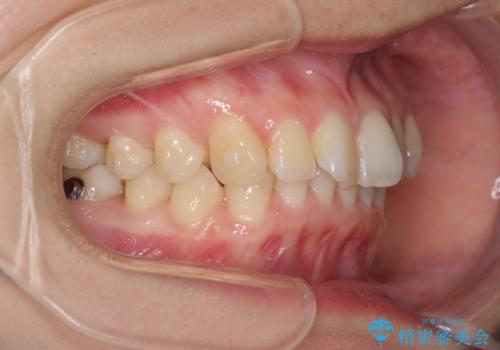

- 口元の深い咬み合わせ(ディープバイト)を気にして来院された患者様です。

インビザラインによる上下歯列の遠心移動(後方移動)により、口元のデコボコとディープバイトを改善することとしました。

下顎左右の犬歯とその後ろにある第一小臼歯、計4歯がシミュレーション通りに動かずディープバイトがなかなか改善されませんでした。

マウスピースの再製作を何度か行いましたがうまくいかないため、部分的にワイヤー矯正を併用することを提案しました。しかし、最も気になっていた前歯のデコボコはきれいに改善されたため、これ以上治療を希望されず、治療を終了することとしました。(今後気になった際には再開する予定です)